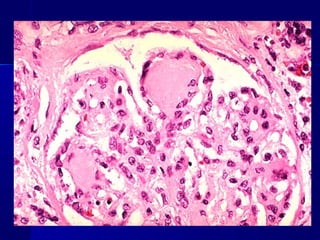

Insulitis en Diabetes Mellitus tipo 1

Insulitis en DiabetesMellitus tipo 1